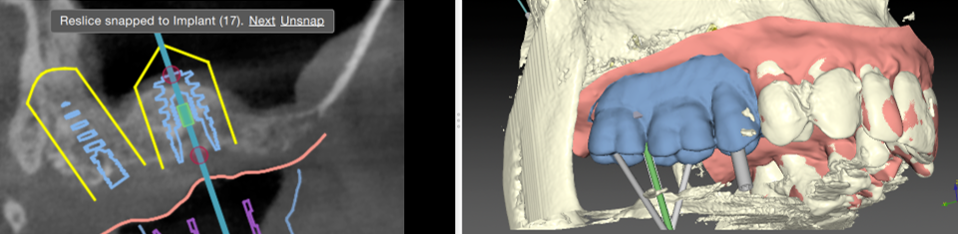

A partir de votre radio 3D réalisée au cabinet, nous lisons votre examen grace à des logiciels permettant une simulation précise du positionnement de vos implants dans l’os.

Cette vision 3D de l’implant dans l’os et en rapport avec les futures dents permet une reflexion « graftless », c’est a dire une implantologie nécessitant un minimum de greffe osseuse, donc plus rapide et moins mutilante.

• Le projet implantaire peut être présenté visuellement au patient avant l’intervention, et les résultats sont prédictibles esthétiquement